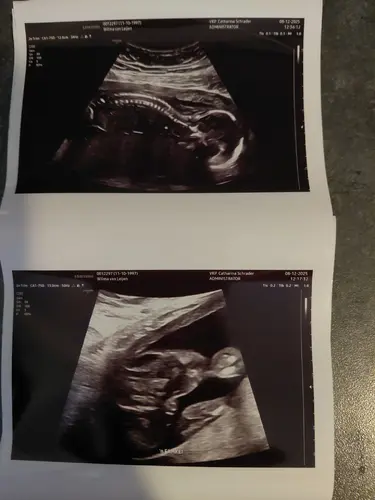

Hier afgelopen maandag gehad met 19+2 weken, ik ben 2 mei uitgerekend. Wij verwachten na een jongetje nu een meisje 馃┓馃グ. De bovenste zie je haar ruggetje heel goed en de onderste is van het geslacht. Wij zijn super blij dat ons zoontje een klein zusje krijgt! 馃┓馃グ